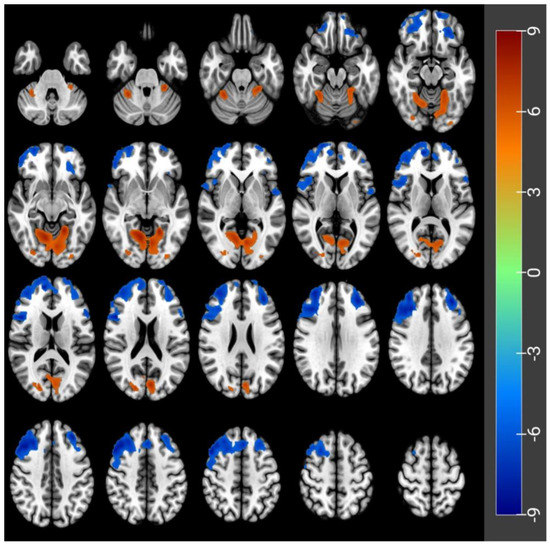

3.3. GMV Differences before and after Acute SD